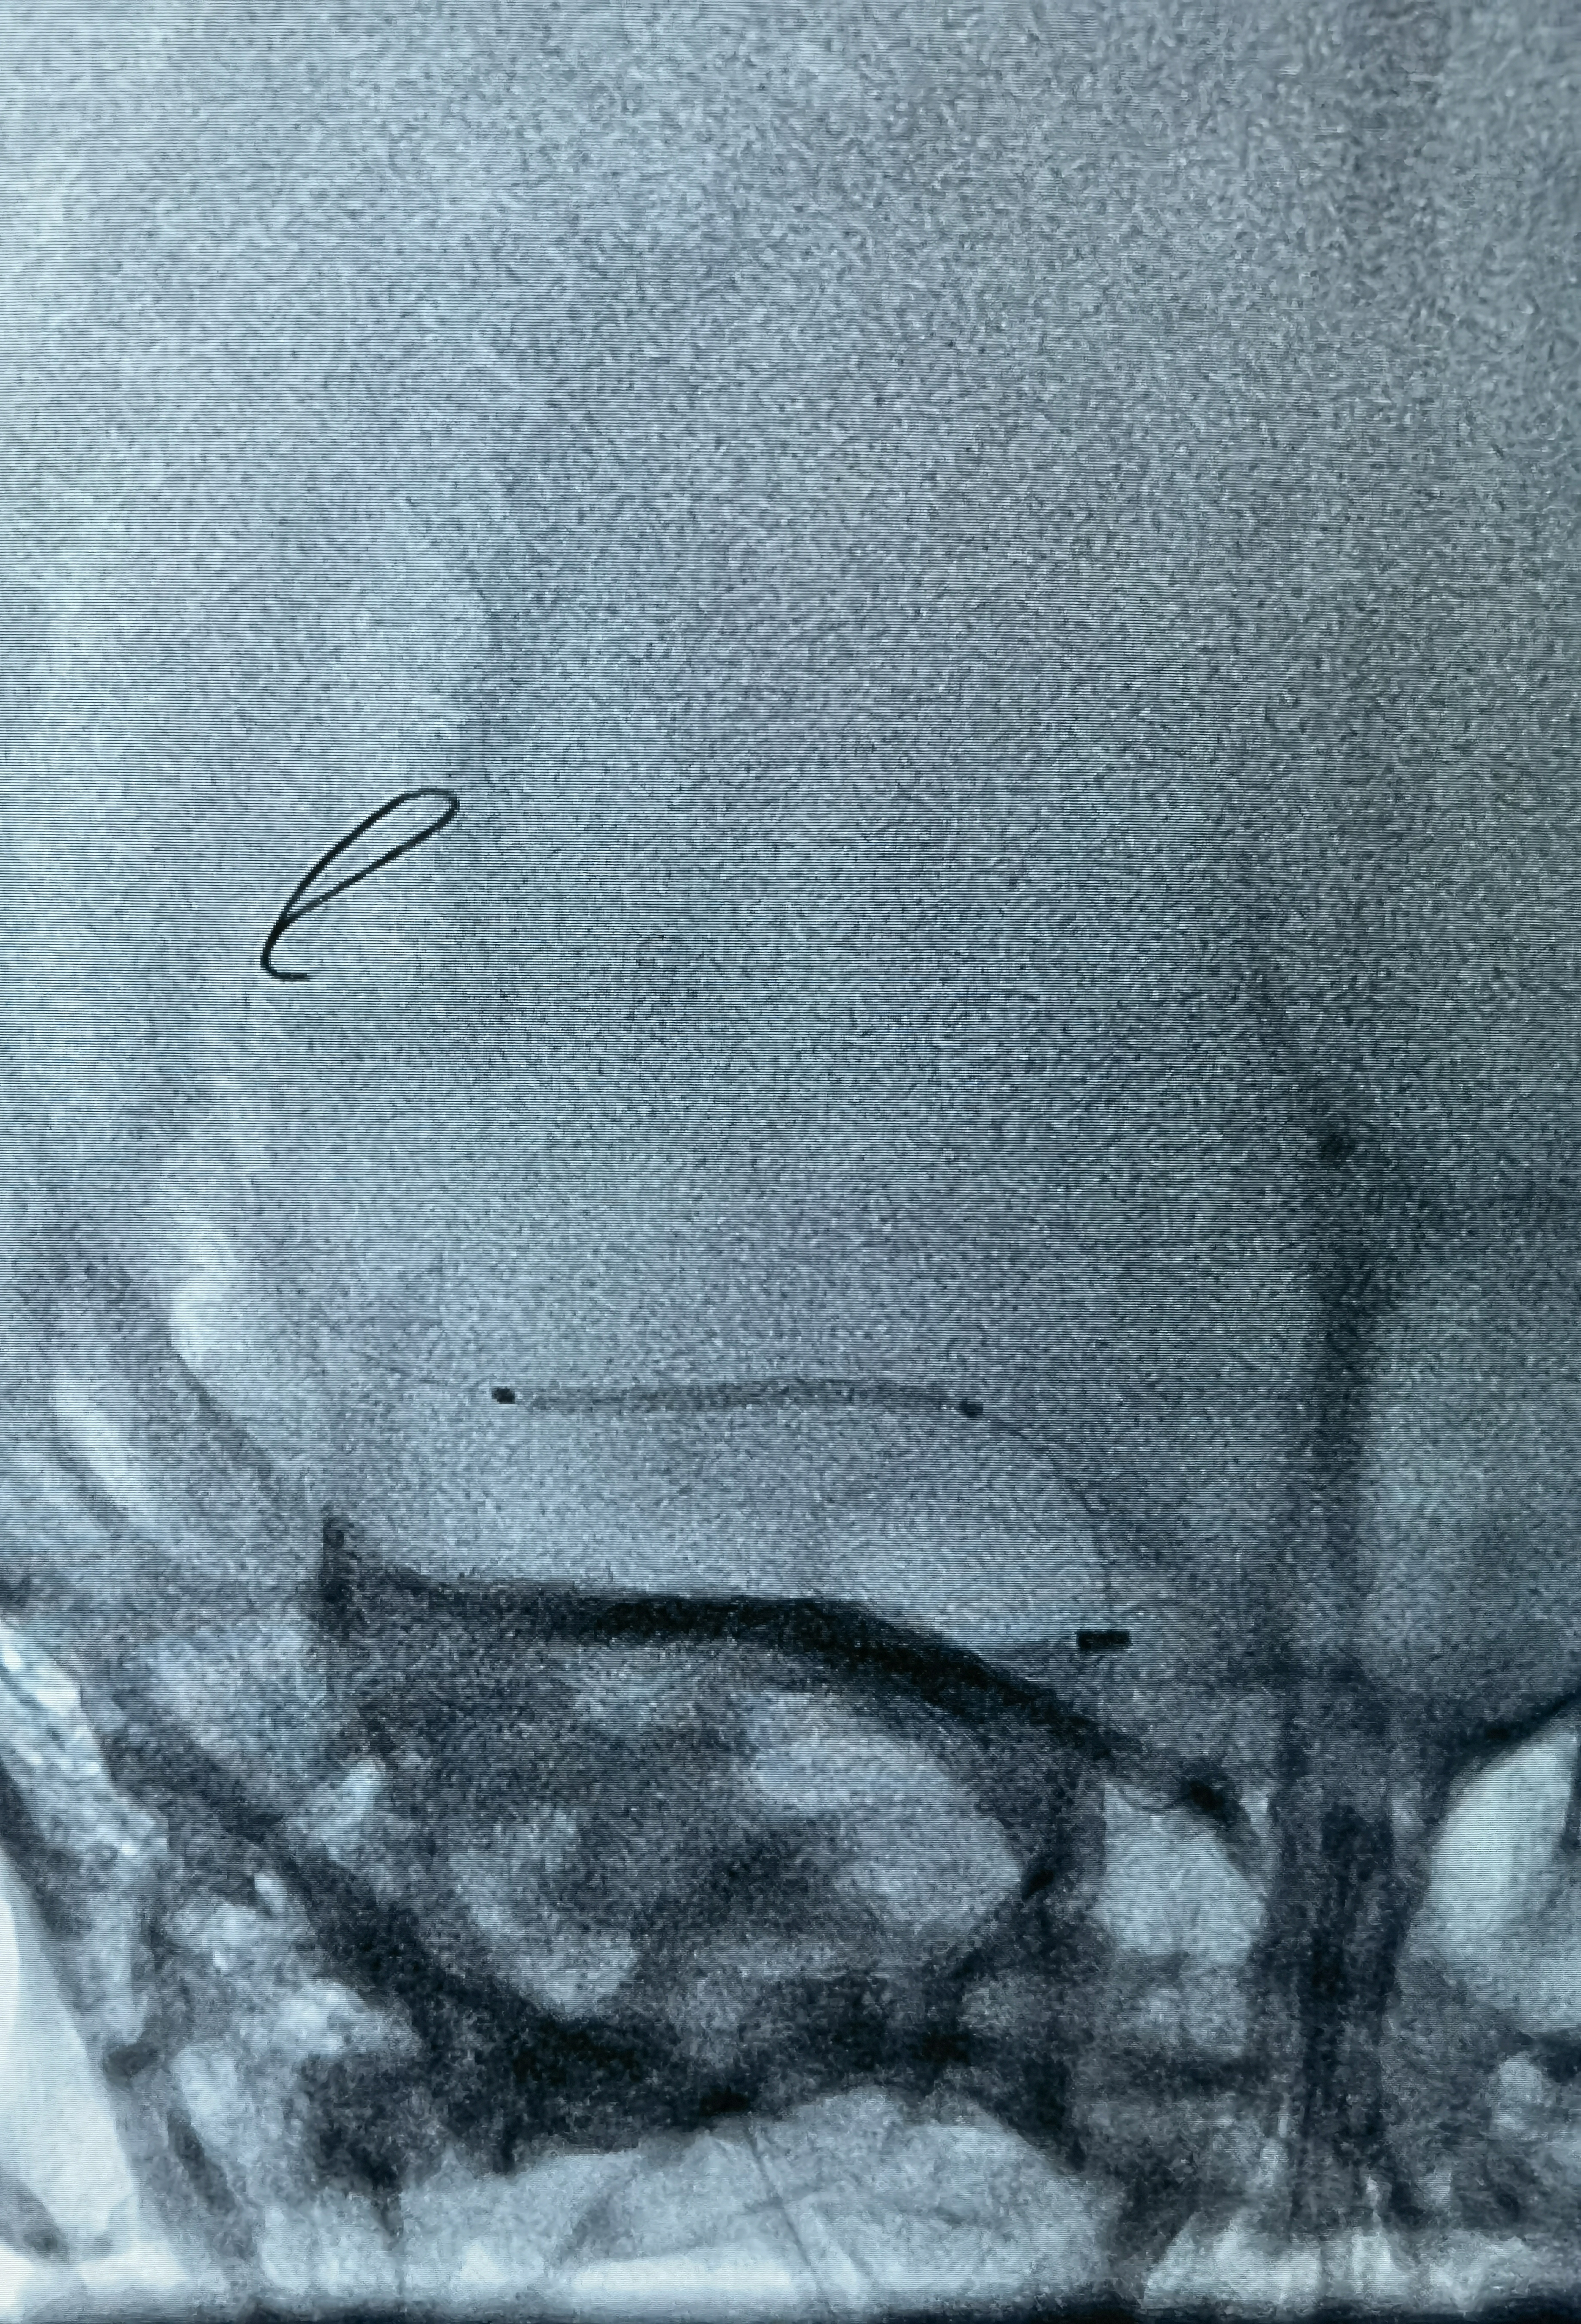

这是术后在影像系统调出来2018年的CTA影像!当时腹主动脉下段已经闭塞了,通过肠系膜上动脉的侧枝以及双侧内乳动脉代偿供血!